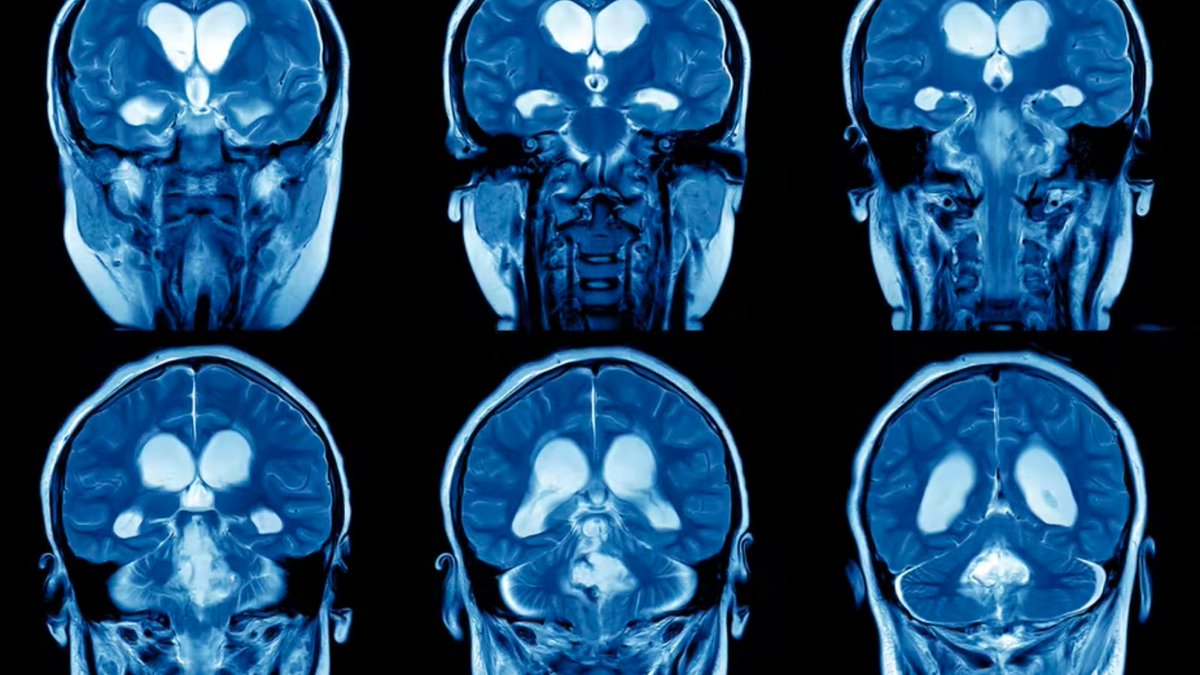

Neuroplasticity, also known as brain plasticity or neural plasticity, is the ability of the brain to change continuously throughout an individual’s life.